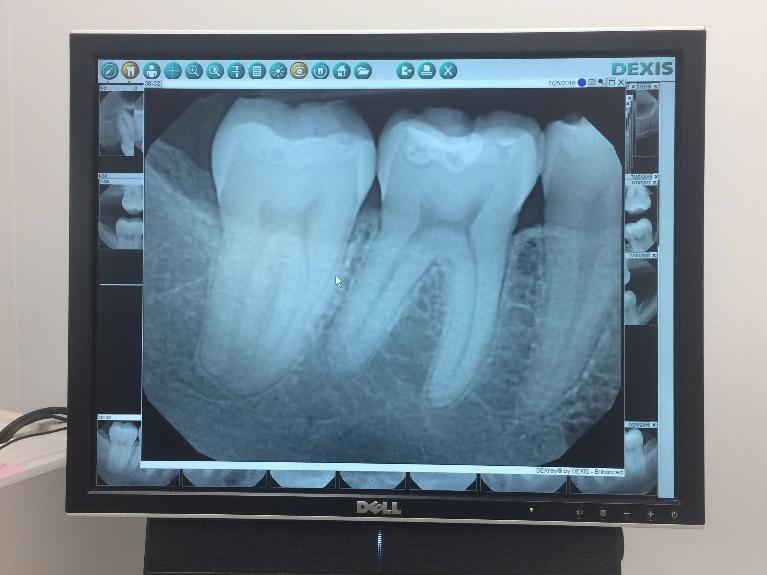

Digital X-Rays

Digital x-rays are an important diagnostic tool. They allow us to detect many common dental issues that start deep within enamel or gum tissue. Digital x-rays allow us to find these problems when they’re small, long before they cause discomfort.

Our patients also like the safety of digital x-rays because significantly less radiation is required to produce these images compared to film x-rays. There are estimates that say digital x-rays reduce your exposure by as much as 80%!

Digital x-rays produce highly detailed images, making it easy to project them directly on our chair side monitors. Dr. Bacquet can manipulate the image, make it larger or smaller, and even rotate it so you can immediately see what the problem is and why treatment is necessary.

Images taken with a digital x-ray can also be stored securely in your patient record. This allows easy access when reviewing your history or sending the images electronically to specialists and insurance providers. Since no chemicals are used to process digital images, they are also better for the environment!